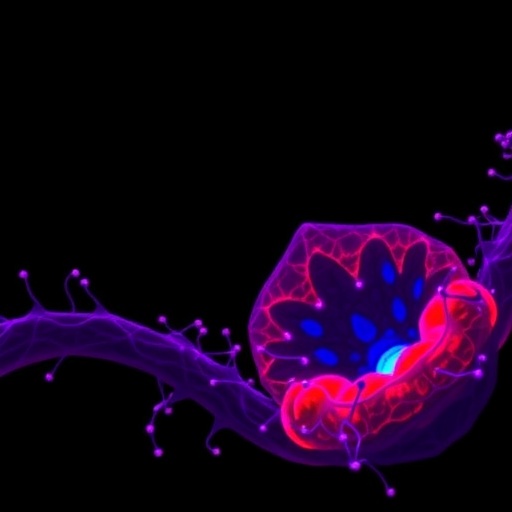

The U2AF1 gene encodes a crucial component of the spliceosome, the cellular machinery responsible for precise RNA splicing—a process that edits pre-messenger RNA into mature transcripts required for correct protein synthesis. Mutations in U2AF1 have been recurrently identified in hematopoietic cancers, notably in myelodysplastic syndromes (MDS) and acute myeloid leukemia (AML). Yet, the mechanistic consequences of these mutations on erythropoiesis, the formation of red blood cells, and their influence on drug responsiveness, remained incompletely understood until now.

Delving deeper, transcriptomic and splicing analyses revealed widespread alterations in RNA splicing fidelity in U2AF1-mutant cells. Key erythropoiesis regulators, including transcription factors and signaling molecules, underwent aberrant splicing, resulting in truncated or nonfunctional protein isoforms. This splicing dysregulation provides a molecular explanation for the impaired erythroid differentiation observed, illustrating how mutations within splicing machinery components can ripple through gene networks to derail normal blood cell development.

This enhanced drug sensitivity possibly stems from epigenetic crosstalk, where splicing abnormalities induced by mutant U2AF1 catalyze specific DNA methylation patterns or chromatin changes that sensitize cells to demethylating agents. The study’s demonstration that pharmacological intervention can partially restore defective erythroid differentiation augurs well for clinical translation, potentially guiding more effective, mutation-specific therapies for patients bearing U2AF1 alterations.